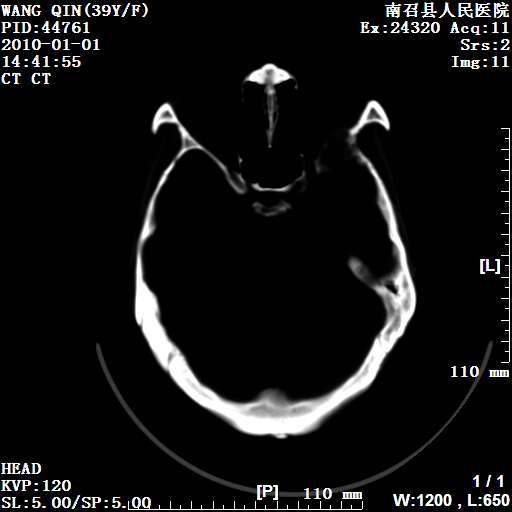

以下是引用随光逐影在2010-1-22 9:03:00的发言:[br]考虑左侧中颅窝(蝶骨翼区)脑膜瘤侵犯蝶骨翼并突入左侧眼眶。

以下是引用水过无痕在2010-1-22 14:55:00的发言:[br]一、定位:颅外占位;二、定性:恶性可能性大;三、组织来源:来源于左侧眼外直肌或其他部位;考虑为:横纹肌肉瘤>转移瘤>脑膜瘤.